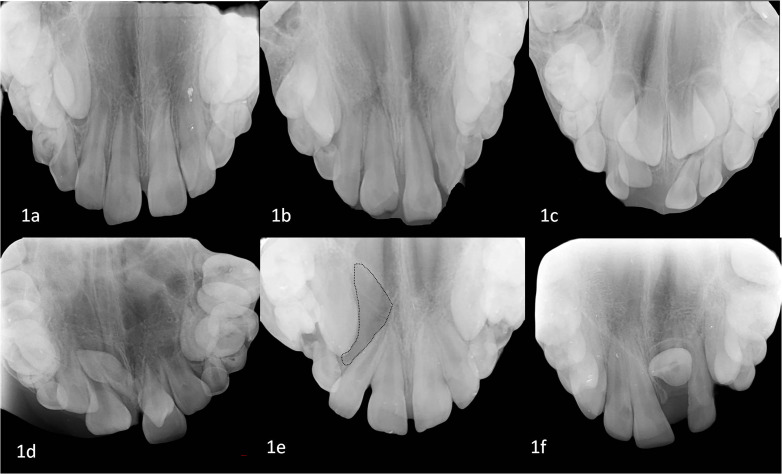

Objectives: Dental radiographs are a useful diagnostic aid in the oral health care and dental treatment of children. The most commonly used radiographs are periapical and panoramic radiographs. Occlusal radiographs are preferred in more specific cases. The aim of this study was to retrospectively evaluate the reasons for obtaining occlusal radiographs in pediatric patients.

Material and methods: Occlusal radiographs of patients aged 1-13 years who attended the Pediatric Dentistry Clinic of Ondokuz Mayıs University Faculty of Dentistry between 01 August 2015 and 01 August 2020 were retrospectively evaluated. Patients with syndromes and diseases that could cause cleft lip and palate and dental anomalies were not included in the study. The medical history of the 354 patients who were included in the study was provided by the automated system.

Results: A total of 359 occlusal radiographs from these patients were analysed. The number of male patients included in the study was 208 and the number of female patients was 146. Occlusal radiographs of the maxilla of 312 patients were taken, of the mandible of 37 patients, and both the upper and lower jaws of 5 patients. It was found that occlusal radiographs were taken mostly for dental trauma in the permanent dentition (156), injuries in the primary dentition (68) and for the diagnosis of dental anomalies (57).

Conclusions: Occlusal radiographs are taken for specific situations in pediatric dentistry and are particularly useful in the detection and diagnosis of primary and permanent tooth injuries.